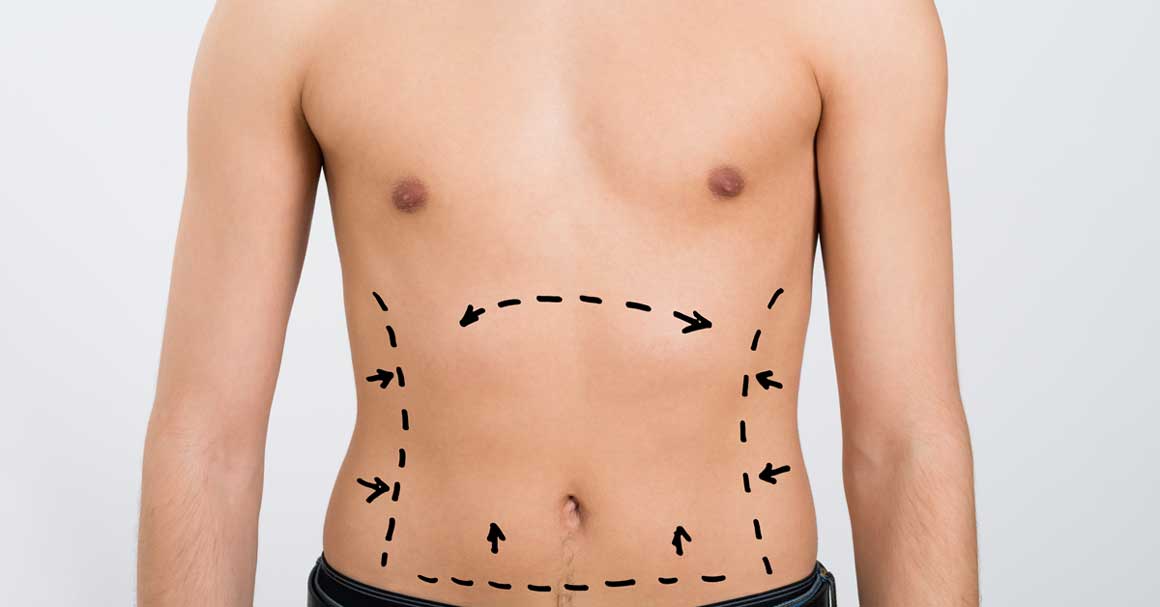

Da li se može javiti celulit kod muškaraca? Odgovor je da! Koliko god da je čudno, celulit kod muškaraca se može pojaviti u svakom životnom dobu. Pročitaj više